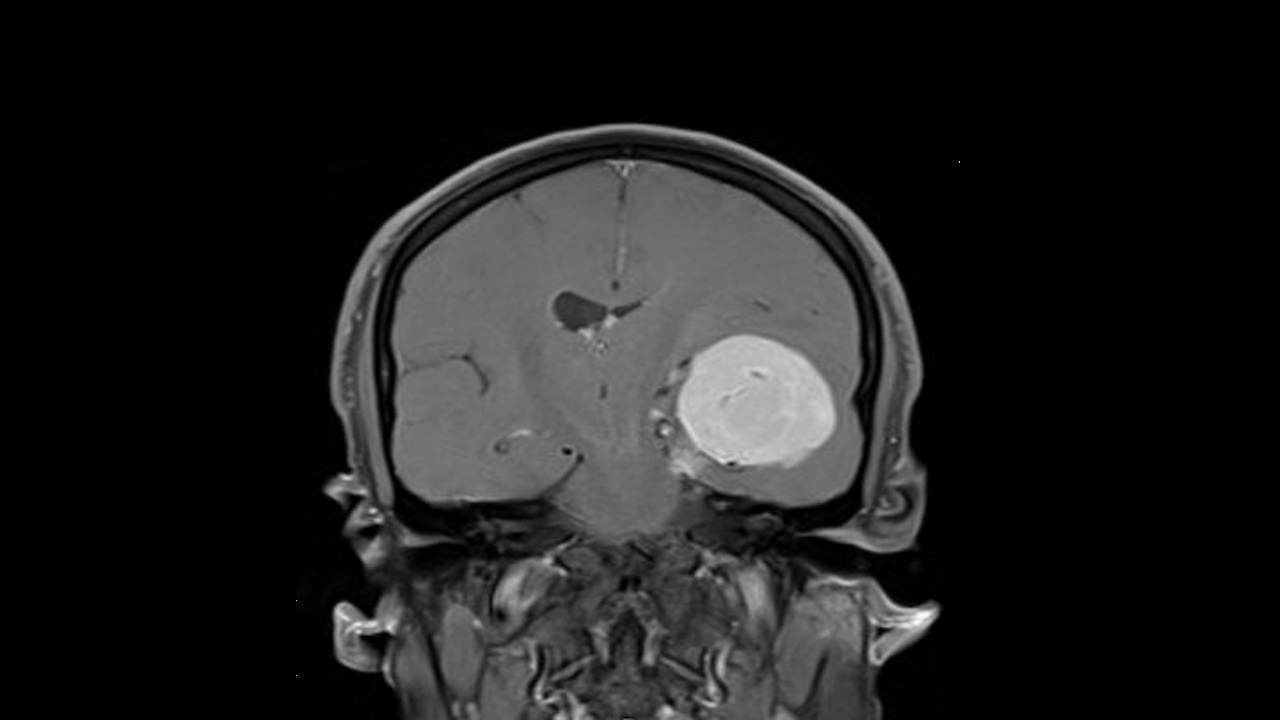

استئصال ورم يساهم في انتشاره

عادة ما يشاع أن استئصال ورم سرطاني يساهم في تعزيز انتشاره، ولكن الخبراء أكدوا أن فرصة حدوث ذلك ضئيلة للغاية.